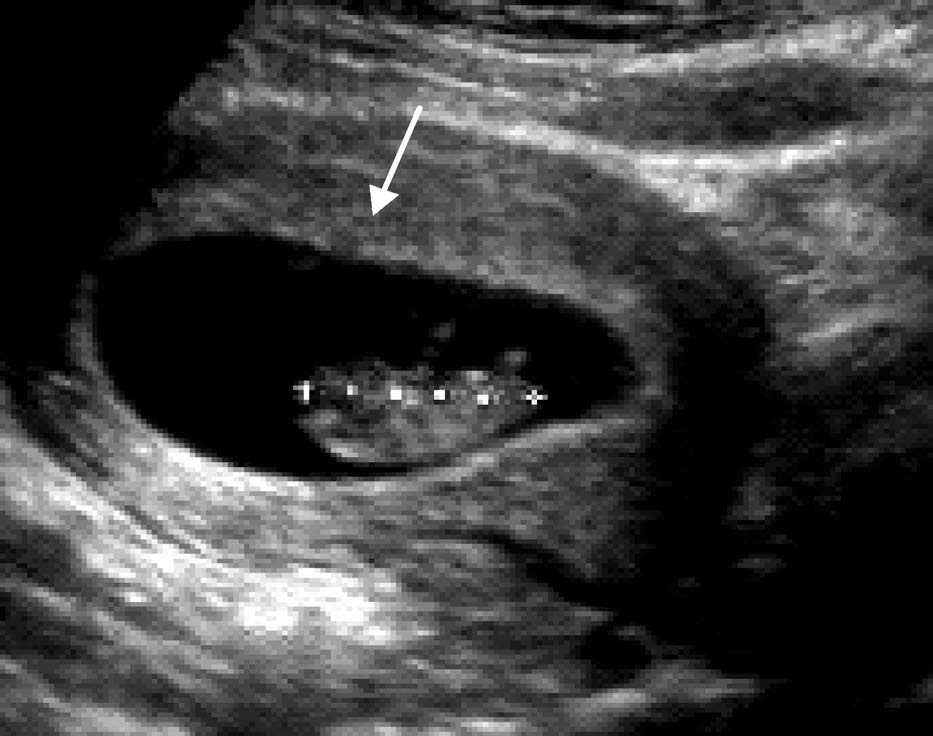

1.妊娠4~5周超声表现:①子宫增大,子宫内膜增厚,内膜内宫腔线的一侧见圆形增强回声区,中央有小囊状液性暗区,为极早期的妊娠囊;②妊娠囊内可见卵黄囊的环形结构,正常直径2.0~5.6 mm;③双蜕膜征或双环征:宫腔少量出血后壁蜕膜和包蜕膜构成的特征性双环结构。检出“双环征”或妊娠囊内见到卵黄囊或胚胎可确定早孕。

患者25 岁。停经35 天,尿HCG(+)。经阴道超声后位子宫纵切面:宫腔内见偏于一侧内膜的圆形囊性结构为胚囊(GS),称偏心圆;囊壁规则,呈中高回声,内部无回声;胚囊前后径2.7 mm;经阴道超声后位子宫横切面:测得胚囊横径为3.0 mm

超声诊断:宫内早早孕。